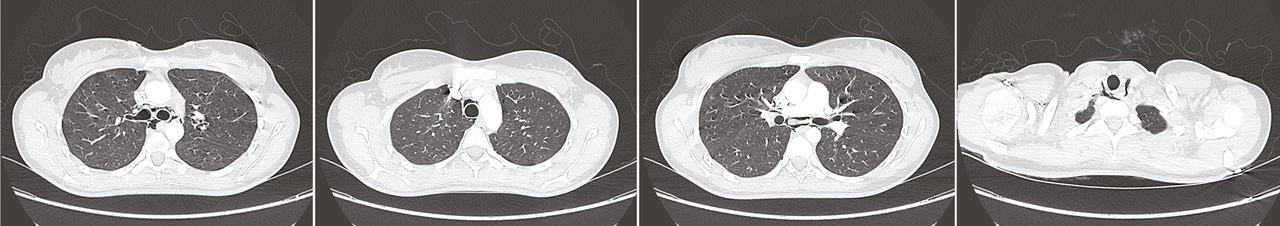

Devant un score de Wells à probabilité faible, les D-dimères sont dosés et positifs. L’angioscanner thoracique montre la présence d’un pneumomédiastin non compressif sans signe d’effraction des voies digestives, trachéales ou bronchiques (figures ). L’image en faveur d’un effet Macklin oriente vers une rupture alvéolaire en lien avec un effort de pression intrathoracique. L’interrogatoire ne retrouve aucun mécanisme déclencheur.

Devant un score de Wells à probabilité faible, les D-dimères sont dosés et positifs. L’angioscanner thoracique montre la présence d’un pneumomédiastin non compressif sans signe d’effraction des voies digestives, trachéales ou bronchiques (

La tomodensitométrie thoracique est l’examen de référence (elle peut montrer l’effet Macklin : présence de collections linéaires d’air, contiguës des axes bronchovasculaires). Elle apporte aussi des éléments de diagnostic différentiel.